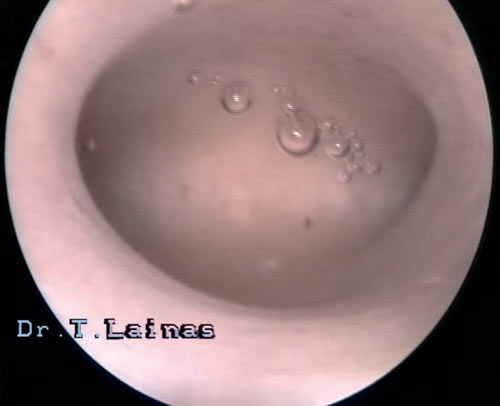

Η κοιλότητα της μήτρας αποτελεί τον χώρο όπου αναπτύσσεται το έμβρυο. Στις δύο άνω άκρες της τριγωνικής κοιλότητας, που ονομάζονται κέρατα της μήτρας, εκβάλλουν οι σάλπιγγες με τα μητριαία στόμιά τους.